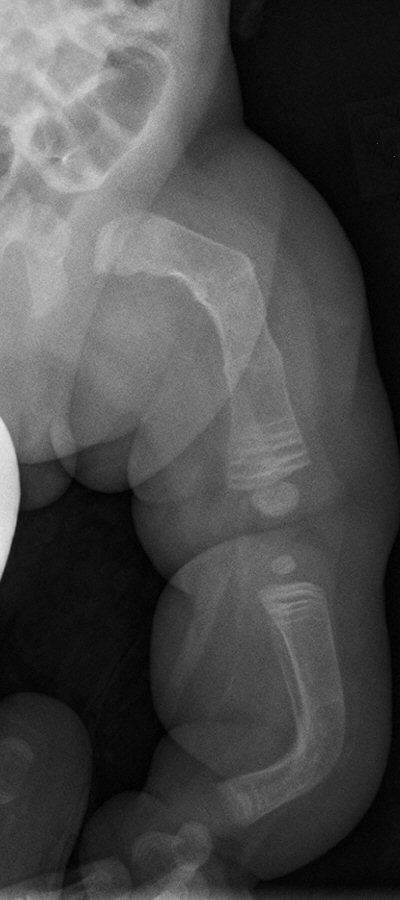

- Upprepade diafysära frakturer

- Deformerat skelett

Barn med osteogenesis imperfecta vid 6 månader, 2 år resp. 7 år